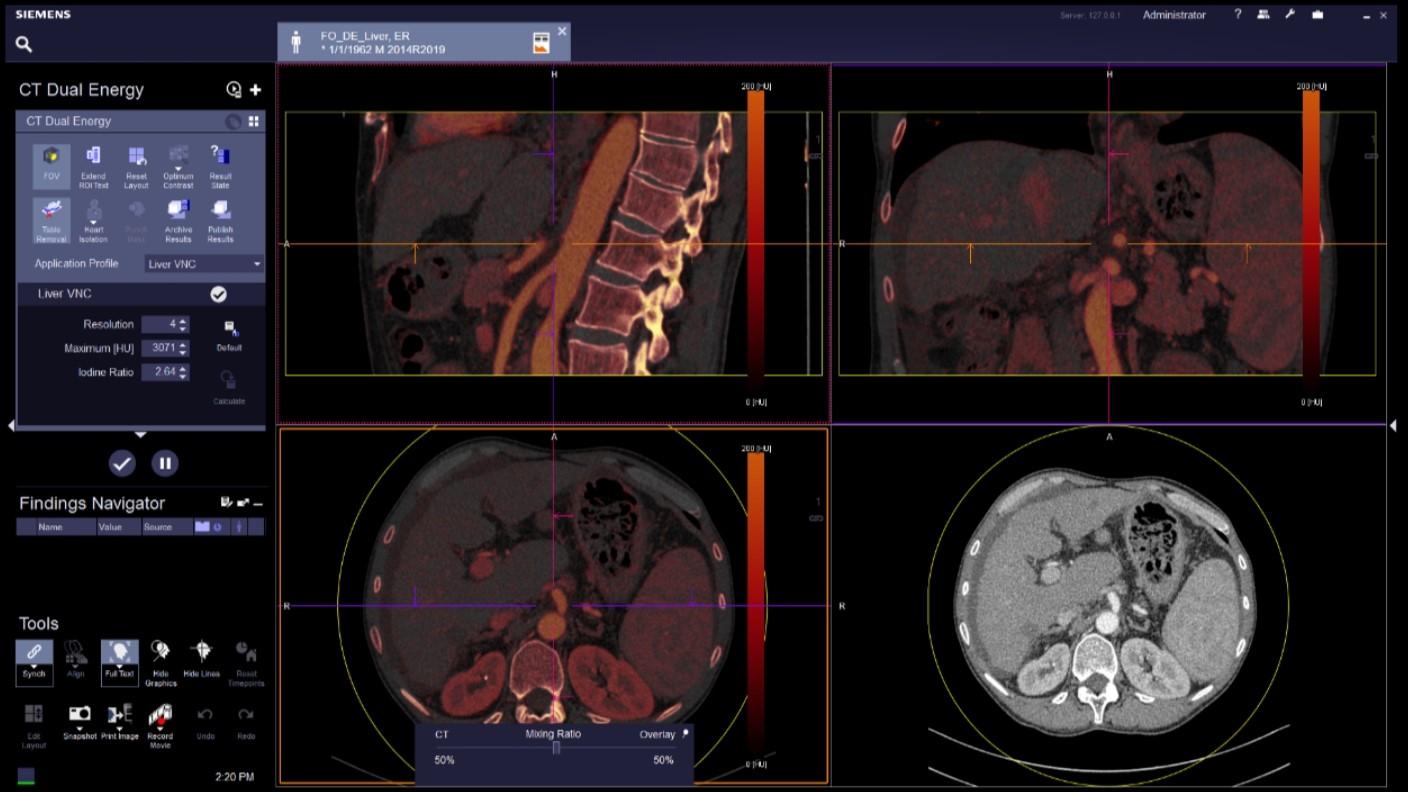

Computed Tomography is moving beyond its traditional diagnostic role to become a key player in early disease detection and therapy planning. This expansion means an even broader patient cohort and resilient productivity demands. You need a reliable partner with products, services, and the infrastructure to support new business models and prioritize environmental sustainability and robustness. Computed Tomography at Siemens Healthineers, with its legacy of listening for almost 50 years, is innovating ahead of these developments, even before potentials become needs.

The NAEOTOM Alpha class